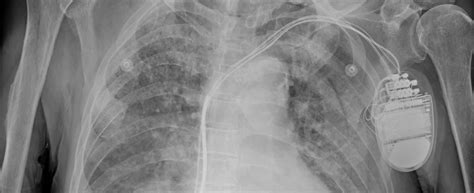

Janet Potter Blog